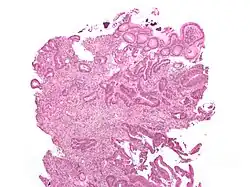

Lâmina histológica de um adenoma tubular, um tipo de pólipo colonial, e um precursor do cancro colorretal.

Em 85% dos casos, o cancro colorretal é precedido por uma lesão benigna conhecida por pólipo. Dependendo da característica deste pólipo, ele pode se tornar maligno e iniciar o cancro. Devido a este processo é que se faz a prevenção deste tipo de tumor com a colonoscopia, já que este exame permite o diagnóstico e a retirada do pólipo. Nos outros 15% dos casos, o tumor ocorre devido a uma doença genética, e se caracteriza por acometer pacientes mais jovens e por não apresentar o pólipo como lesão pré-maligna, ou seja, surge diretamente na parede do intestino.